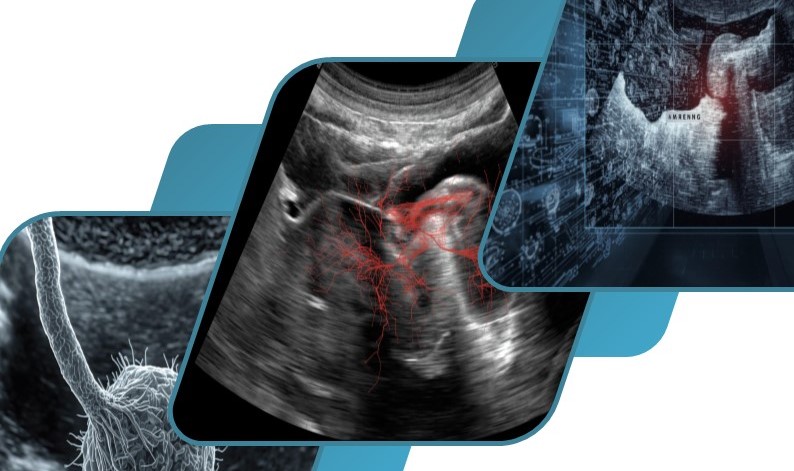

This invention relates to diagnostic ultrasound imaging, specifically employing a compressed sensing approach to enhance image quality while reducing channel count and data load.

- Efficient Channel Reduction

- Enhanced Image Recovery

- Enhanced Contrast Imaging